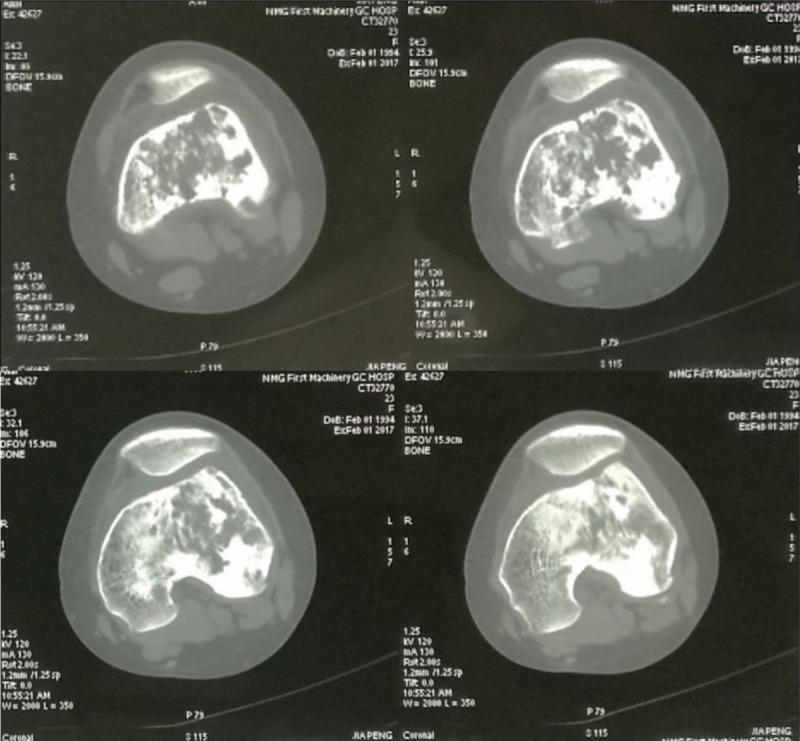

PATIENT CONCERNS

A 25-year-old female patient was consulted in the Armed Police General Hospital (Beijing, China) due to repeated pain in the right thigh lasting over 1 year. Imaging examination revealed a space-occupying lesion in the right femur.

骨促结缔组织增生性纤维瘤(DFB)是一种极为罕见的良性骨肿瘤,可发生于任何骨骼,可见于任何年龄段。在此,我们报告一例具有非特异性影像学表现的病例。

患者情况

一名25岁女性患者因右大腿反复疼痛超过1年就诊于武警总医院(中国北京)。影像学检查发现右股骨有占位性病变。

在本病例报告中,我们描述并强调了所检查病例的特殊性以及一些DFB病例影像学结果可能存在的非特异性。